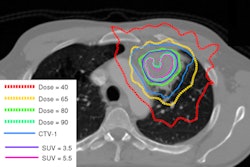

The study describes OCT morphology in nonmelanoma skin cancer (NMSC) lesions during PDT and assesses how OCT morphology before, during, and after treatment reflects the treatment outcome at three-month followup.

The VivoSight scanner uses OCT to provide images of subsurface tissue similar to ultrasound, but at a greater resolution, enabling the clinician to see critical details of the skin epidermis and dermis in real-time.